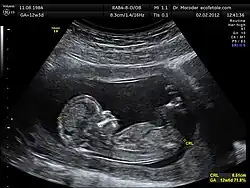

O ultrassom é usado em diversos campos. Dispositivos ultrassônicos são usados para detectar objetos e medir distâncias. Ultrassonografia é usada tanto em medicina veterinária quanto em medicina humana. Em testes não destrutíveis, o ultrassom é usado para detectar falhas em produtos e estruturas. Industrialmente, o ultrassom é usado para limpar, misturar e acelerar processos químicos.

Aplicações Biomédicas

O ultrassom também tem aplicações terapêuticas que podem ser altamente benéficas se usado com precaução. Potências de ultrassom relativamente altas podem desmanchar depósitos de pedras e tecidos, acelerar o efeito de drogas em uma área alvo, auxiliar na medição das propriedades elásticas do tecido, e pode ser utilizado para classificar células e pequenas partículas para pesquisas.

Usos na medicina

- Ultrassonografia

- Ecografia